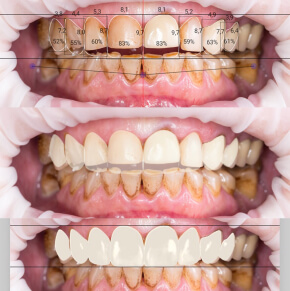

Komputerowe projektowanie uśmiechu

Co powinnaś wiedzieć o smile design?

Stomatologia estetyczna to dziedzina zajmująca się poprawą wyglądu zębów i estetyki uśmiechu. Jeśli chcesz odmienić swój uśmiech i skorygować niedoskonałości, skontaktuj się z nami! Przygotowaliśmy specjalny protokół, który pomoże nam zaplanować leczenie. Dotyczy on także większych prac protetycznych

Konsultacja SMILE DESIGN (ok 1.5h) obejmuje:

- Dokładny wywiad z pacjentem, wysłuchanie jego oczekiwań oraz powodów niezadowolenia z wyglądu swoich zębów (np. przebarwienia, stłoczenia, przerwy między zębami, zęby zbyt małe lub duże, braki zębowe itd.)

- Badanie zębów i całej jamy ustnej.

- Oprócz rutynowego przeglądu stomatologicznego badamy estetykę i przebieg linii uśmiechu, kształt zębów, zgryz.

- Odniesienie estetyki zębów do wyglądu całej twarzy, postury pacjenta, karnacji oraz wieku (np. dłuższe zęby przednie eksponowane w uśmiechu odejmą Ci wiele lat, sprawią, że będziesz wyglądać młodziej).

- Wykonanie zdjęć (fotografii) twarzy oraz uśmiechu.

- Wyciski diagnostyczne zębów, które wraz ze zdjęciami przesyłamy do laboratorium protetycznego. Technik protetyk wykonuje na modelach tzw. WAX UP, czyli ręcznie wymodelowany z wosku wygląd Twoich nowych zębów. Posłuży on w późniejszym etapie jako matryca do wykonania tymczasowych uzupełnień.